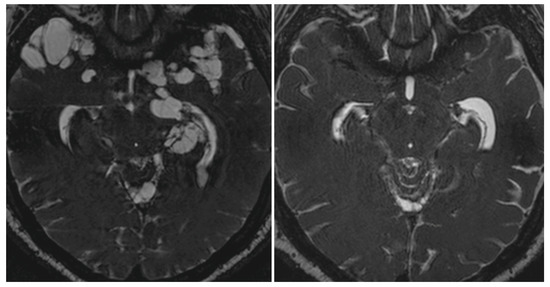

Treatment of extraparenchymal NCC is complicated since many patients do not respond to traditional doses of cysticidal drugs. In these cases, increased dosages, prolonged administration, or repeated drug trials may be needed to destroy the cysts (Figure 2). However, no randomized controlled trials confirming the benefits and risks of therapy for extraparenchymal NCC have been published, and all the available evidence is based on expert opinion and non-controlled trials [31,62,63,69].

Figure 2.

Fast Imaging Employing Steady-state Acquisition (FIESTA) MRI sequence showing massive cysticercal infection of the base of the brain and temporal pole by subarachnoid cysticerci (left) and their disappearance six months after cysticidal drug therapy (right). Courtesy of the Cysticercosis Working Group in Perú.